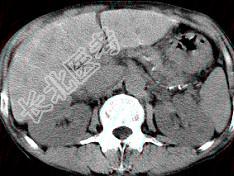

- 单项选择题男,40岁有血吸虫感染史,腹胀不适,食欲减退,CT扫描所见如图,最可能的诊断是 ( )

A、肝炎后肝硬化

B、血吸虫后肝硬化

C、酒精性肝硬化

D、胆汁性肝硬化

E、脂肪肝